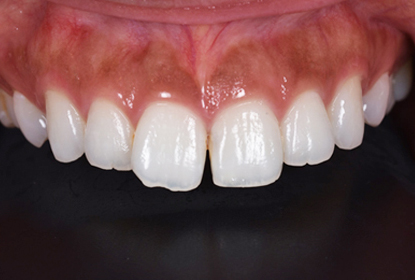

初診時

患者様の主訴は、「前歯の隙間が気になる」

でした。

矯正治療をおすすめしましたが、矯正治療の期間が長いということでセラミック治療を選択することになりました。写真をみるとすきっ歯も気になりますが、以前に詰めたプラスティックも変色して着色しており気になります。

仮歯

セラミックの前に仮歯を調整している段階になります。できればということで歯の長さも短くしたいというリクエストがありましたので、仮歯で調整をしながら様子を見ました。

歯の長さを短くする際に歯を削りますので神経の治療が必要になることがありますので、しみたり・噛んで痛くないか?を約1ヶ月様子を見ました。色・形など仮歯でほぼ問題ないということでしたので、最終的な型採りをしました。